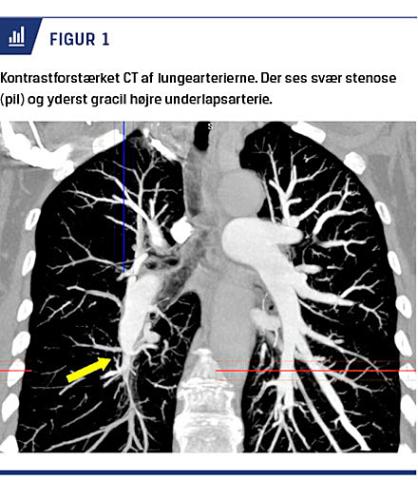

Den endelige diagnose baseres på påvisning af prækapillær pulmonal hypertension (middelpulmonalarterietryk ≥ 25 mmHg, pulmonary capillary wedge pressure < 15 mmHg, pulmonary vascular resistance (PVR) > 3 Wood Units (WU)) samt visualisering af karakteristiske obstruktive forandringer i pulmonalarterierne ved CT-lungeangiografi (Figur 1) og DSA (Figur 2). Hos patienter med akut lungeemboli bør diagnosen CTEPH først stilles efter minimum tre måneders antikoagulansbehandling, idet der i denne tidsperiode er chance for resolution af tromboembolimaterialet og klinisk bedring.